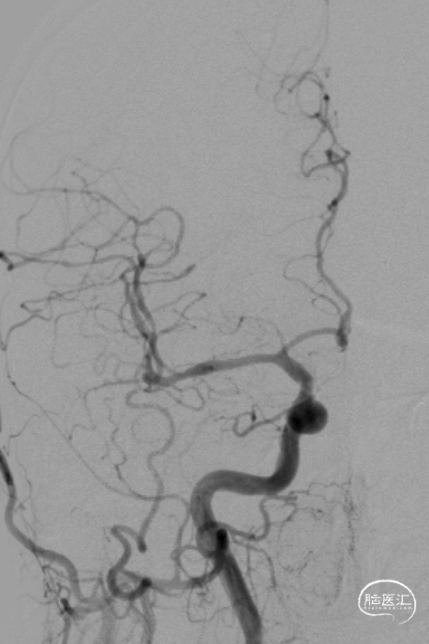

超选右侧椎动脉造影:右侧椎-基底动脉连接处次全闭塞,前向血流 mTICI 2b级。

最后影像:椎基底动脉连接处残余狭窄约20%,前向血流改善明显,mTICI3级。远端各血管显影良好,分支较术前增多。